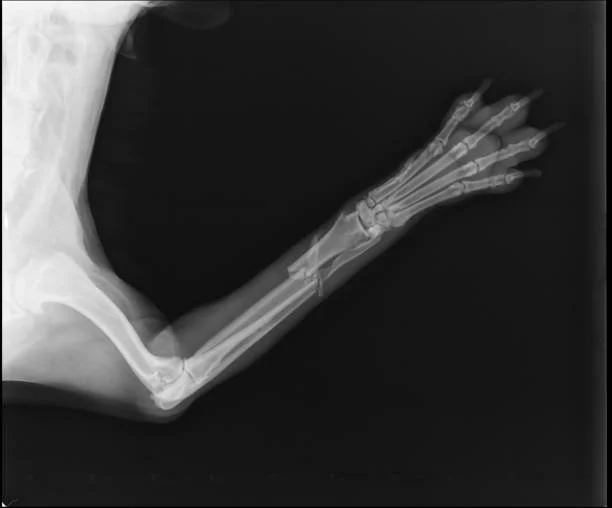

Physical Therapy can help rehabilitate patients after fractures/breaks, whether they have been surgically repaired or conservatively managed.

When there is a fracture to a limb, and your pet is not bearing full weight, the muscles in the leg begin to constrict and tighten, which reduces their range of motion and balance. Physical Therapy helps to reduce and reverse the effects of this, in addition to reducing inflammation and providing some pain relief.